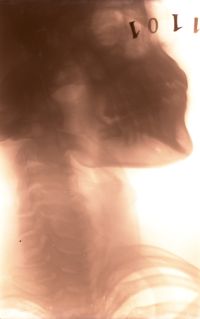

Image[Radiographie. Tête, cou de profil, bouche fermée.]